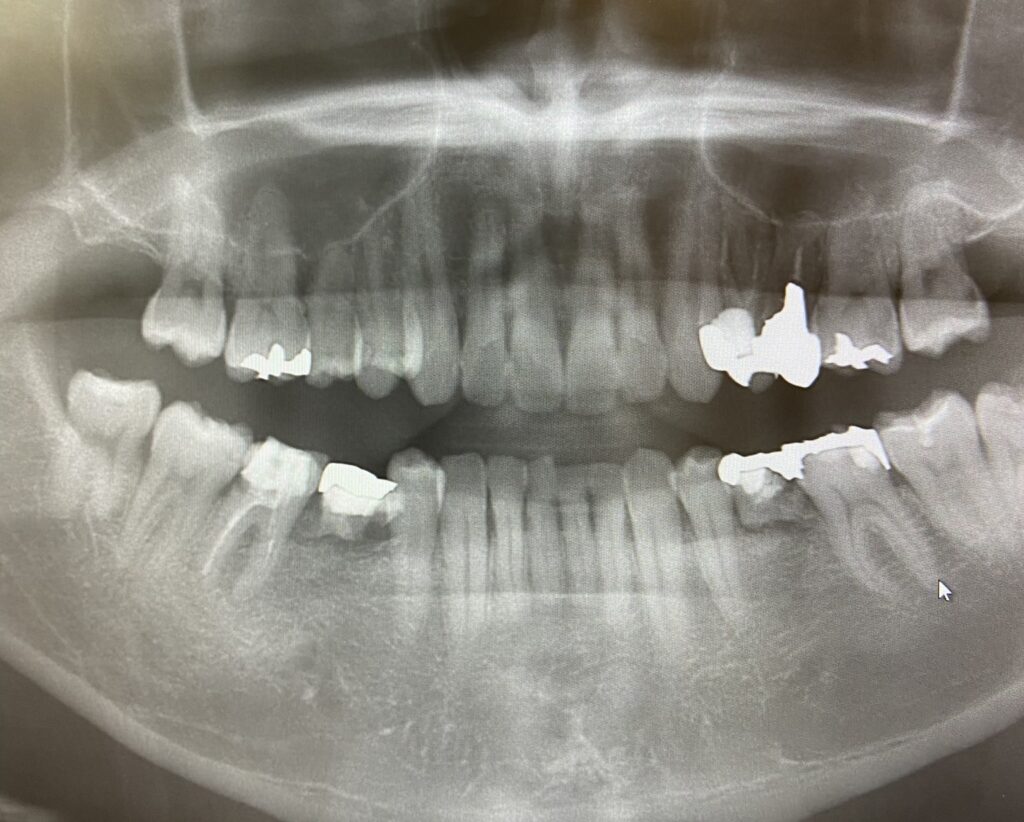

歯科で利用されているレントゲン写真は、主にパノラマエックス線写真とデンタルエックス線写真の2種類です。

パノラマエックス線写真は、お口全体の様子がよくわかるのですが、細かなところは写らないので、小さい初期虫歯を見つけ出すのは困難です。

パノラマエックス線写真でお口全体をチェックして、細かなところをデンタルエックス線写真でチェックするという方法が行われますが、それでも初期虫歯が写し出されないこともしばしば起こります。

レントゲン写真なら確実にわかるように思われがちですが、初期虫歯では必ずしもそうではないというところも、虫歯の判断を難しくしています。